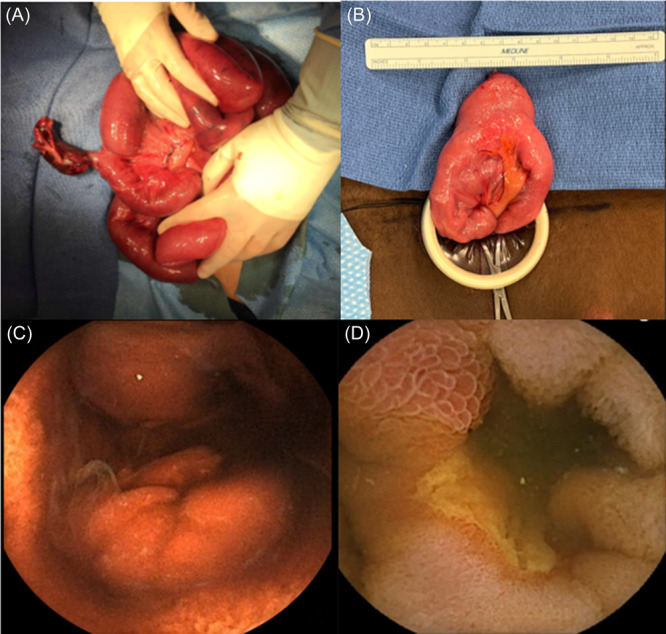

Abstract Image